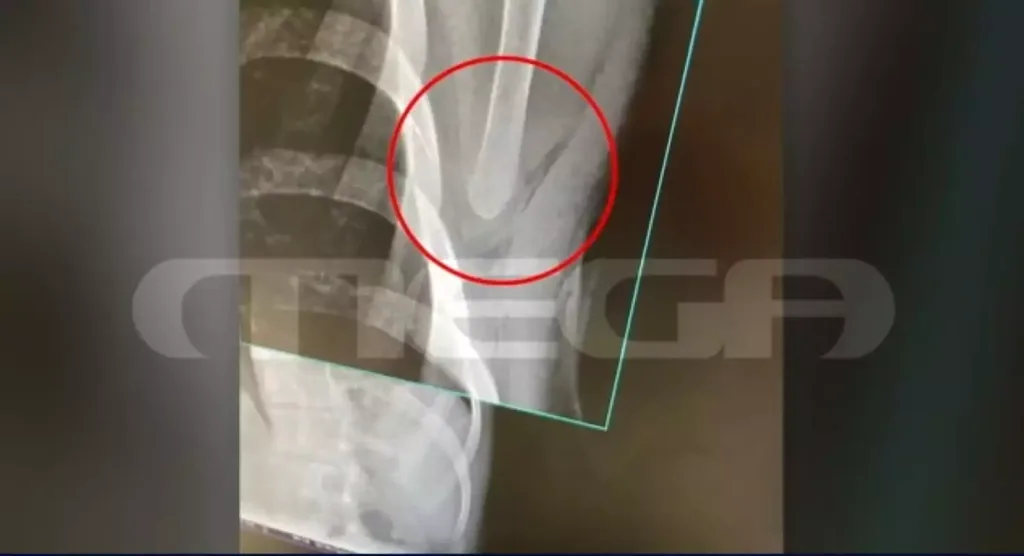

FacebookShare on XBlueskyEmailCopy LinkΈνας νεαρός στη Γλυφάδα βίωσε τον απόλυτο τρόμο, όταν δέχτηκε επίθεση για μια φαινομενικά ασήμαντη αφορμή, με αποτέλεσμα να πέσει θύμα ξυλοδαρμού και να δεχτεί επίθεση με κατσαβίδι. Το περιστατικό αφορά έναν 21χρονο, ο οποίος ήταν σταματημένος σε φανάρι όταν κοίταξε το διπλανό αυτοκίνητο. Οι επιβάτες του άλλου οχήματος παρεξήγησαν τη ματιά … Συνεχίστε να διαβάζετε το Γλυφάδα: 10 άτομα επιτέθηκαν με κατσαβίδι σε 21χρονο- Σοκαριστικά ντοκουμέντα (vid).